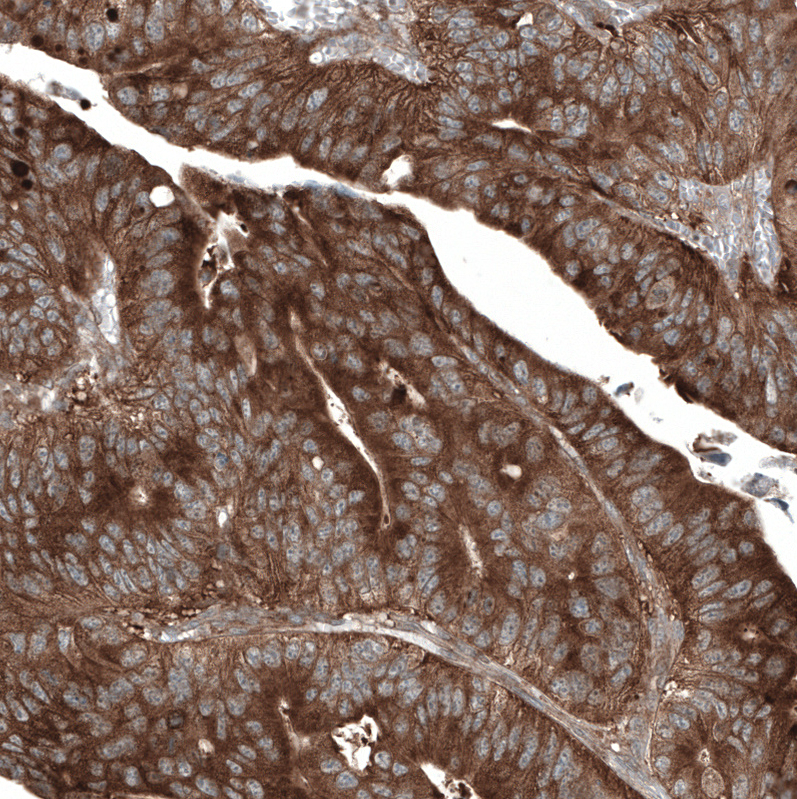

Immunohistochemical staining of human breast cancer shows strong cytoplasmic positivity in tumor cells.